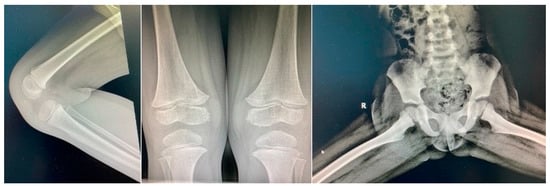

Three weeks later, the patient came back with fever and left knee swelling with partial function impairment within 24 h of onset. His mother also described, two days prior, a non-itching maculo-papular cutaneous rash on the chest and belly, which disappeared spontaneously. Clinical examination did not encounter anything out of the ordinary (no fever, no rash), just mild painful swelling of the left knee. Laboratory investigations were also, this second time around, in the normal range. Borrelia infection was excluded. The orthopedic exam did not describe local inflammatory signs and joint mobility and knee X-rays were normal (Figure 3). He received oral anti-inflammatory medication.

Figure 3. Normal bone X-rays.